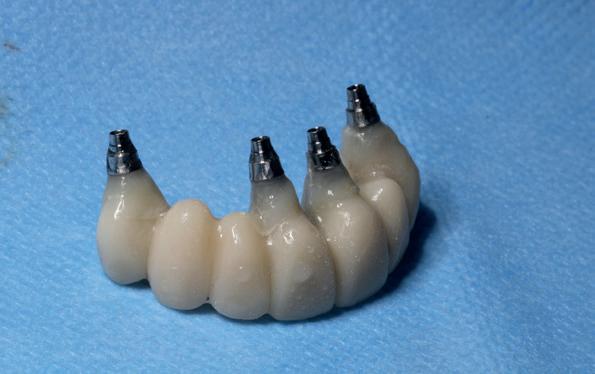

In de prothetische fase (zie foto’s) is in de bovenkaak gebruikgemaakt van verschroefde zirconia bruggen, die enkel buccaal zijn opgebakken. Deze bruggen zijn verlijmd op individuele, geanguleerde titanium abutments. In de onderkaak is een verschroefde kunststofbrug op een titaniumbasis (wrap-around) gemaakt. Voor deze combinatie is gekozen vanwege een minder hinderlijk tikkend geluid bij functie en kleinere kans op breuk van de keramiek. Een nadeel is verhoogde slijtage van de kunststof elementen, maar deze zijn in de jaren later eenvoudig te vervangen op de bestaande brug. Ondanks alle digitale mogelijkheden is de afdruk en registratiefase analoog uitgevoerd, omdat in ervaring van de behandelaren dit bij deze totale rehabilitaties op implantaten nog altijd de grootste precisie oplevert. Er is afgedrukt met impregum in individuele lepels en de pasvorm is gecontroleerd met rigide duralay bars. De relatie wordt vastgelegd zoals bij een volledige prothese met waswallen en pijlpuntregistratie. De opstelling in was wordt gepast en laatste correcties worden gemaakt in samenspraak met de patiënt, de restauratieve tandarts en de tandtechnicus. Na het vastzetten van de suprastructuren worden de schroefgaten afgesloten met composiet.

10. In de bovenkaak is gekozen voor 3 zirconium bruggen; in de onderkaak is gekozen voor een wrap-around met titanium

core.

11. In de bovenkaak is keramiek gebruikt en in de onderkaak kunststof (behandeling is

uitgevoerd met restauratief tandarts Paul de Kok, KVPA). 12. Eindresultaat.